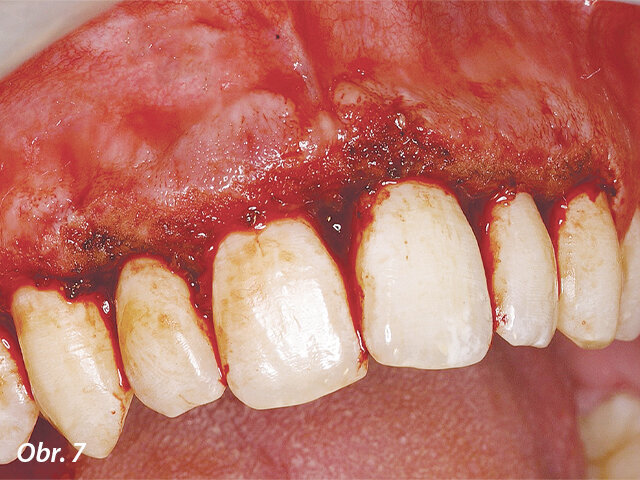

V druhé kazuistice se jednalo o dospívajícího pacienta s hyperplastickou gingivitidou v horním frontálním úseku.

Odstraňování nežádoucích hyperplastických tkání pomocí diodového laseru AMD Picasso s jednorázovým hrotem.

Po odstranění hyperplastických tkání v horním frontálním úseku byl patrný posun směrem k požadovaným výsledkům.